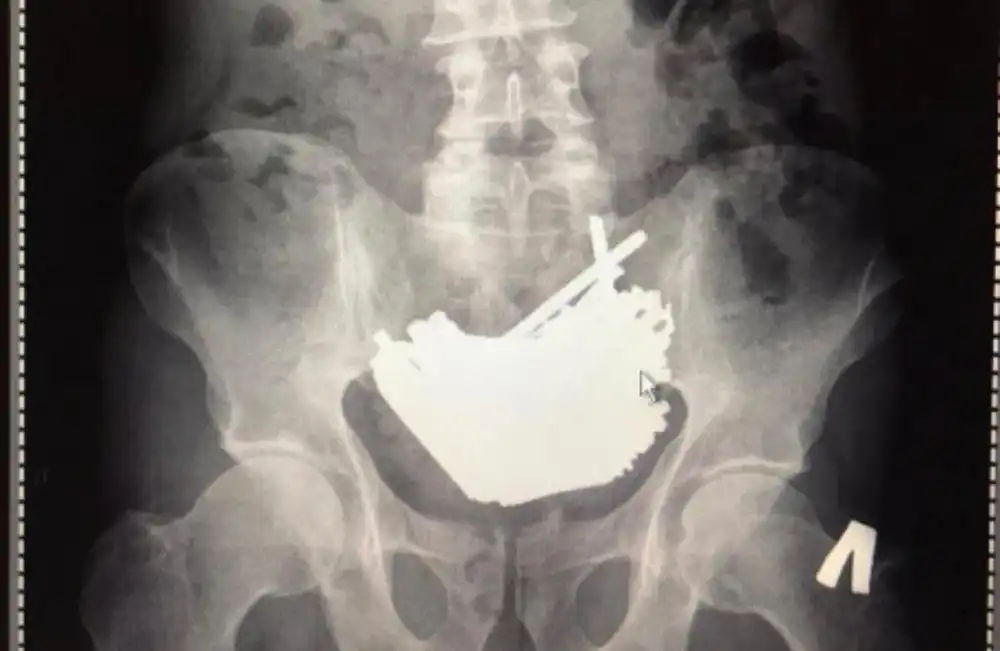

Отправили на снимок, а там вот такое чудо – 875 грамм отличных шурупов! 112 штук. Причем носил их он аж четыре месяца.

Зачем глотал? Сам не знает. Просто глотал. Помимо шурупов нашлись еще мелкие гвозди, разрезанные саморезы и даже щипчики для ногтей. Часть в желудке, часть в кишечнике. И большая часть стального груза может быть и вышла бы естественным путем, но этот придурок до кучи проглотил еще и магнит (!!!!!), который всё стянул в один комок.